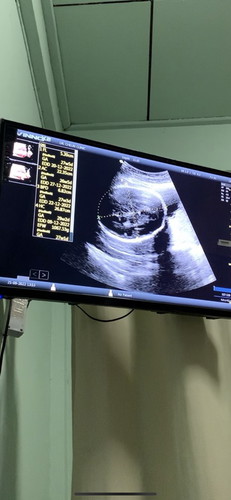

น้อง 28 วีค หัวไม่กลม

คุณหมอบอกว่าหัวน้องไม่กลมค่ะ แม่ๆบ้านไหนเคยเจอแบบนี้ไหมคะ อันตรายไหมคะ ที่ผ่านมาอัลตราซาวด์น้องหัวกลมตลอดเลยค่ะมาช่วง28วีคไปตามนัดอัลตราซาวด์หมอบอกว่าหัวน้องไม่กลมเหมือนเดิม แม่เครียดและกังวลมากค่ะ😢 #ขอคำแนะนำหน่อยค่ะ #คุณแม่ๆช่วยแนะนำหน่อยค่ะ